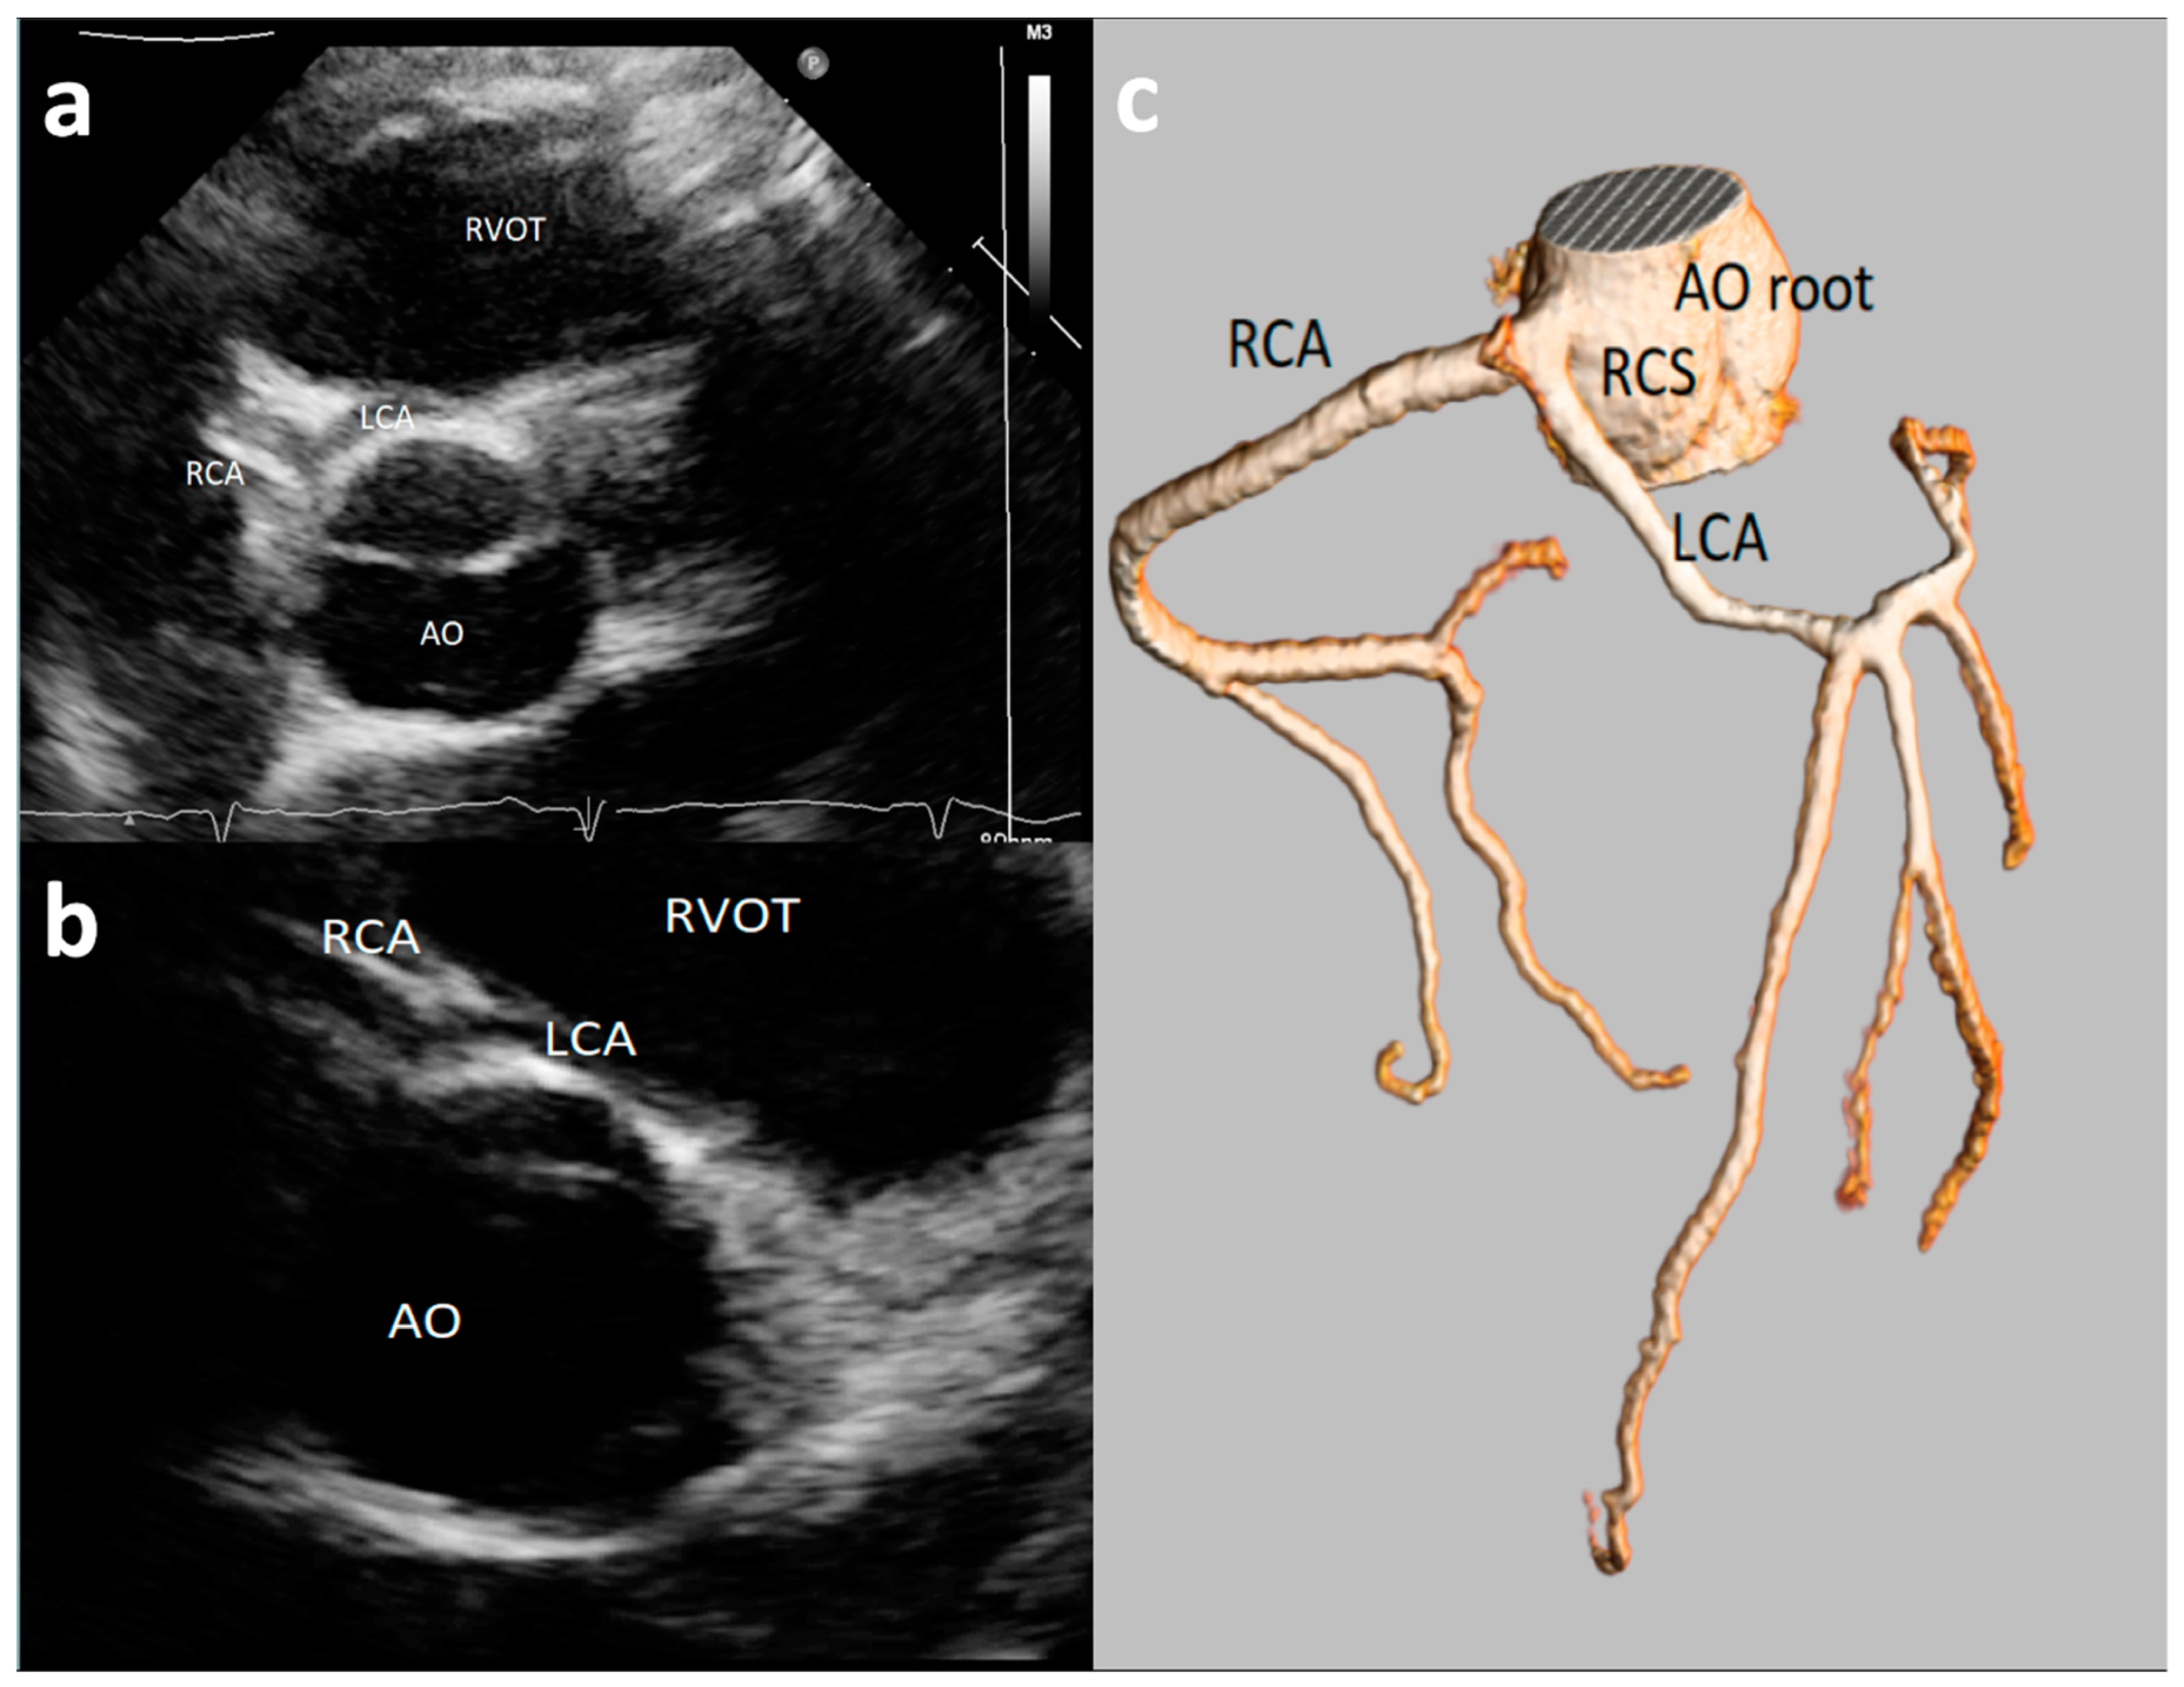

Major AAOCAs were usually defined as RCA and LCA origins from opposite wrong sinus (Figure 1), a single ostium coronary artery, or left circumflex artery (CFx) originating from right coronary sinus [14,15,20,23,24,31]. The detection rate of major AAOCAs greatly varied among the different studies, from 0.0% [15,24,31] to 0.09% [20] and up to 0.76% [23]. The positive predictive value of echocardiography (with confirmation at either coronary angiography or CT angiography) in the diagnosis of major AAOCAs was high, varying from 87.5% [21] to 100% [20].

Figure 1. An asymptomatic 14-year-old boy evaluated with negative stress test for murmur at routine soccer screening. Origin of the left common artery (LCA) from the right sinus of Valsalva was incidentally discovered at echocardiography ((a,b)—short-axis view with slightly different angulation) and confirmed by Coronary Computed Tomography Angiography (CCTA) (c). RCA = right coronary artery; LCA = left common artery; RCS = right coronary sinus; AO = aortic root; RVOT = right ventricle outflow tract.